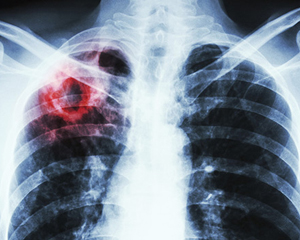

У 2020 р. в Україні зареєстрували 17 593 випадки захворювання на активний туберкульоз, включно з рецидивами. Про це повідомляють у Центрі громадського здоров’я МОЗ України та зазначають, що це на 29,8% нижче, ніж у 2019 р., тоді зареєстрували 25 237 випадків.

У розрахунку на 100 тис. населення захворюваність знизилася із 60,1 до 42,2.

Найвищі рівні захворюваності на туберкульоз зареєстровано серед населення Одеської (2 171 випадок), Дніпропетровської (2 005), Львівської (1 098) областей та підконтрольної Україні частини Донецької (1 065) області.

Водночас у Тернопільській області зафіксували найбільше зниження захворюваності — на 48,9%. Також помітне зниження в Чернівецькій (43,8%), Івано-Франківській (41,9%), Вінницькій (39,4%) областях та місті Київ (37,8%).

Захворюваність на активний туберкульоз, включно з рецидивами, серед дітей віком 0–17 років у 2020 р. знизилася на 32,1%. У 2019 р. показник захворюваності становив 10,6 на 100 тис. населення, а 2020 р. — 7,2 на 100 тис., або 803 та 540 в абсолютних числах відповідно.

Захворюваність на туберкульоз у поєднанні з ВІЛ/СНІДом у 2020 р. знизилася на 35% — до 2 860 випадків порівняно з 4 398 — у 2019 р. (відповідно до 6,9 з 10,5 на 100 тис. населення).